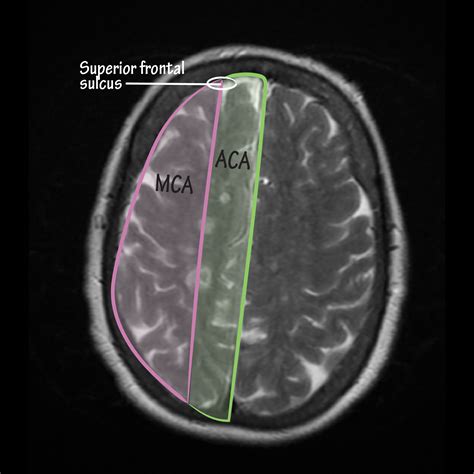

• Cortical Watershed Zones: These occur on the outer surface of the brain, specifically in the regions where the anterior cerebral artery (ACA) meets the middle cerebral artery (MCA), or where the MCA meets the posterior cerebral artery (PCA).

MRI (Diffusion-Weighted Imaging) The gold standard for identifying acute ischemic lesions in the border zones.